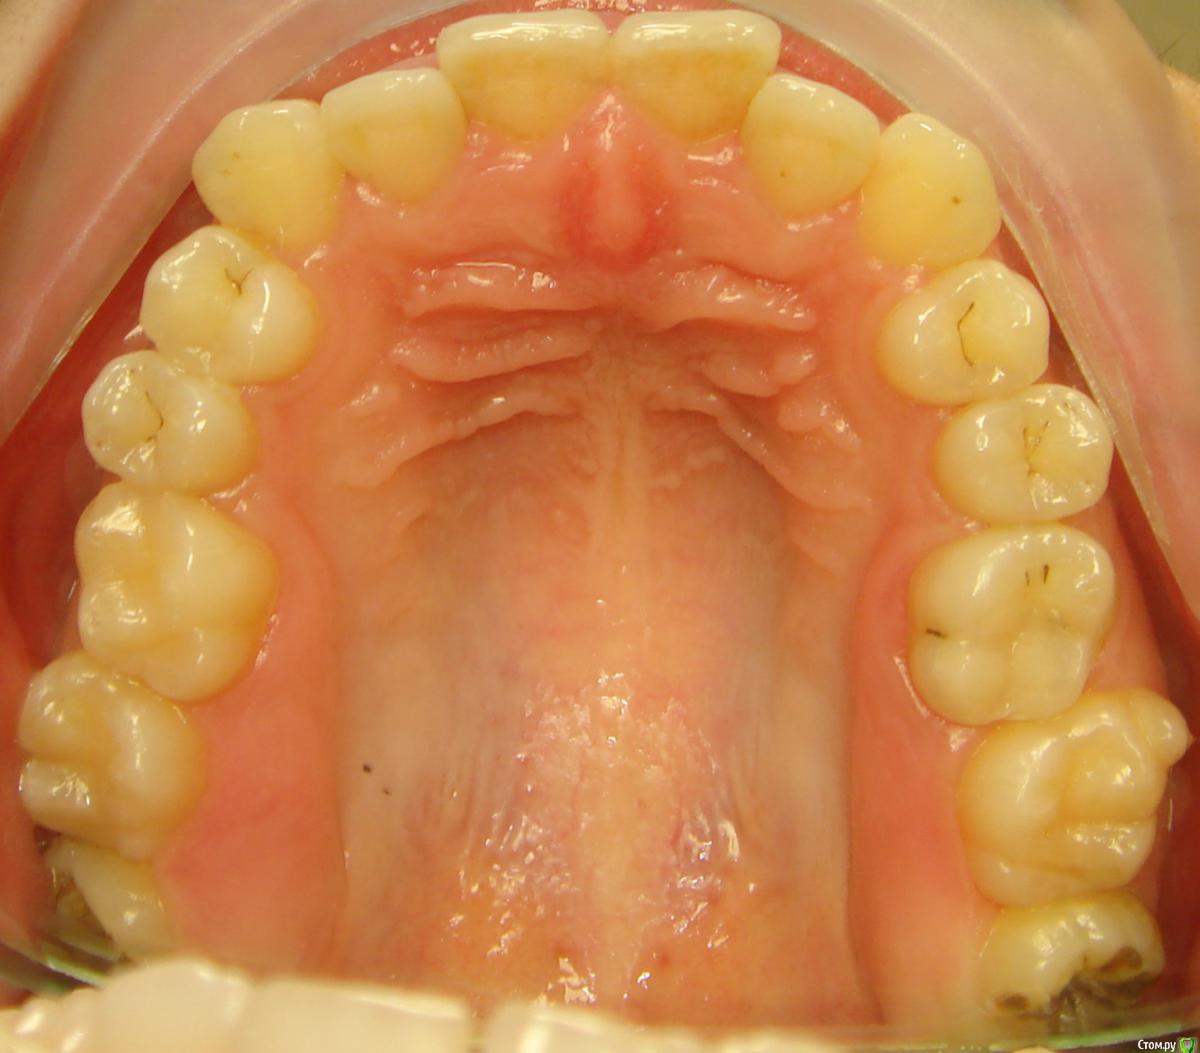

Opdihatop Опубликовано 10 декабря, 2016 Поделиться Опубликовано 10 декабря, 2016 Добрый вечер, коллеги! У меня вопрос к тем, у кого опыта по MEAW больше, чем у меня. Пациентка, 24 года, на данный момент все зубы мудрости удалены, привычная окклюзия по резцам - край в край. Сам процесс я понимаю, но есть несколько нюансов, которые хотелось бы уточнить:1) Нивелировать ли просто фронт в/ч, как книжка пишет (просто поставить дугу и все), или все-таки немного дистализировать боковые участки? С одной стороны простое нивелирование ускорит процесс и облегчит перебрасывание резцов, с другой стороны я опасаюсь чрезмерной протрузии из-за выравнивания дистопированных клыков; но при этом дистализация усугубит 3-й класс.2)Какой высоты делать окклюзионные накладки, в книжке они минимальные, а мне как то хочется побольше, чтобы резцы разомкнуть почти край в край, но не испортит ли это биомеханику?Буду очень благодарен вам за помощь! Ссылка на комментарий

Opdihatop Опубликовано 10 декабря, 2016 Автор Поделиться Опубликовано 10 декабря, 2016 P.S.: на хирургию пациентка согласна, но только, если мультилуп не сработает. Ссылка на комментарий